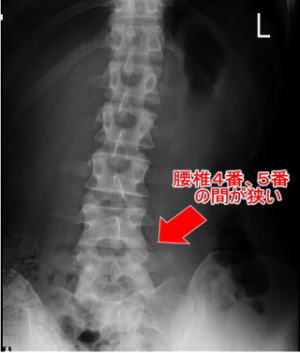

施術後 施術後の腰椎

施術前:腰椎が右に傾き、4番と5番の間が狭くなり椎間板が飛び出している

施術後:腰椎が真っ直ぐになり、4番と5番の間が広がり椎間板も凹み、腰痛が消失

※副院長自身の椎間板ヘルニアの写真です

Afterは最初の施術から4ヶ月後の写真です

※すべての方に同様の変化を保証するものではありません